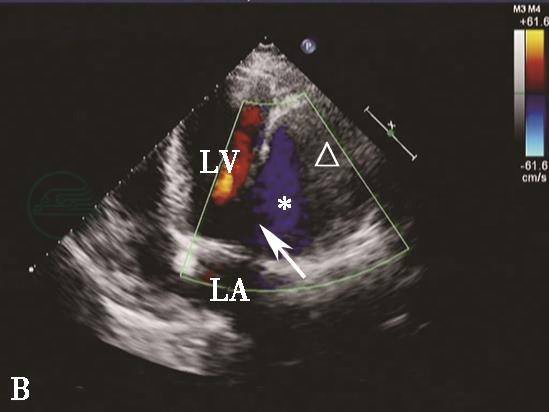

图6心肌梗死后室间隔穿孔彩色多普勒血流图像

A.彩色多普勒血流图像显示胸骨旁非标准切面室间隔心尖部穿孔处(箭头示)左向右分流信号;B.二尖瓣短轴切面后间隔基底部穿孔处(箭头示)左向右分流信号。LA.左心房;LV.左心室;RV.右心室。